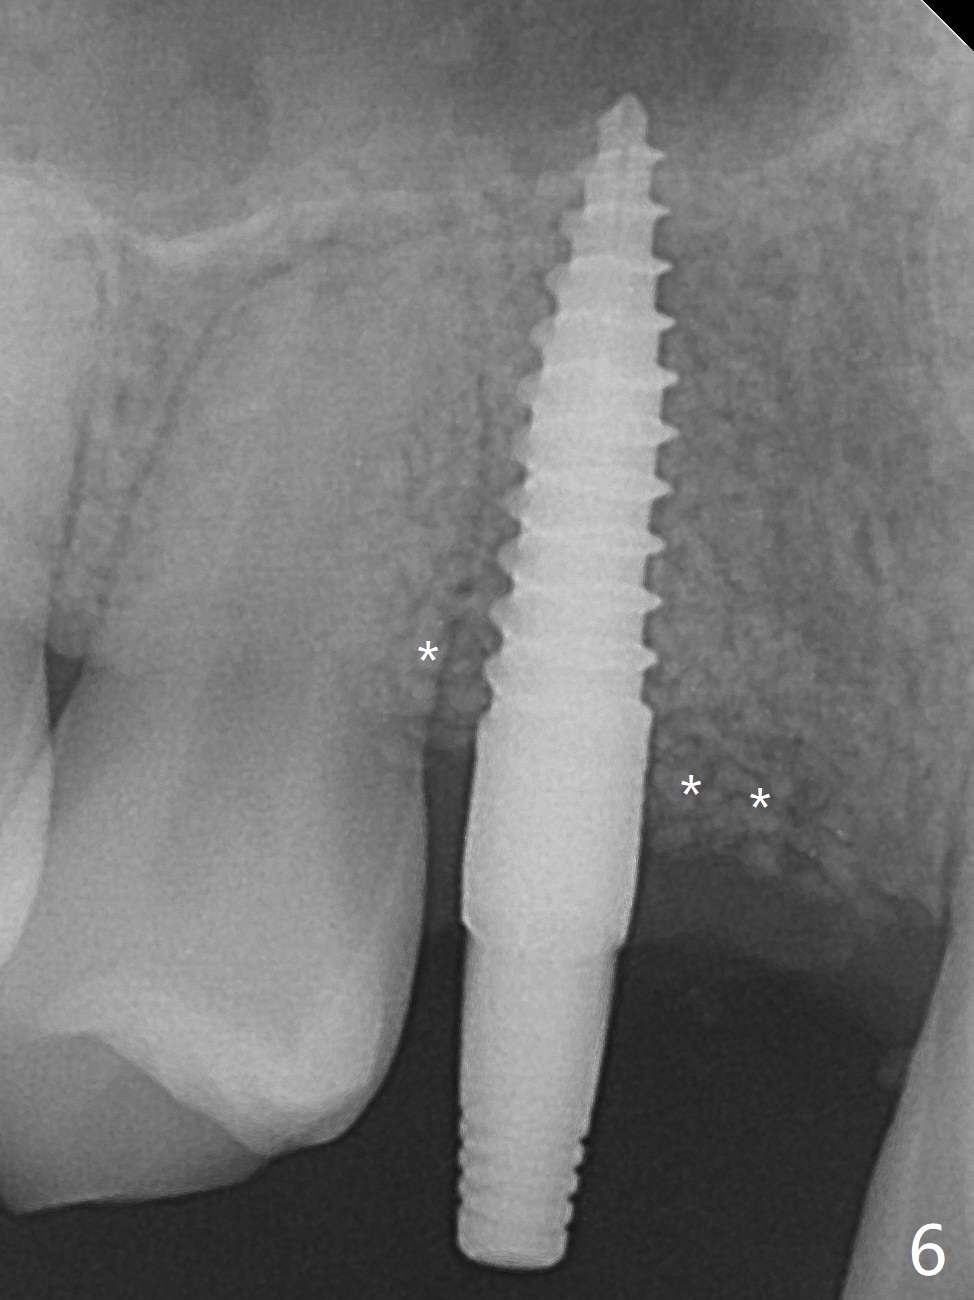

右上尖牙植体拔除,植骨后6个月,切开显示不可吸收膜覆盖的牙槽骨尚饱满(图一),不可吸收膜下面形成一个膜(可能是骨膜,图二:M),在导板指导下,植入3x12(2)毫米一段式植体,颊侧(图三),腭侧(图四)骨下,稍微穿过窦底(图五),植体覆盖粘性骨粉(图六)和PRF膜后,4-0 PGA缝合。伤口有一定张力,使用牙周敷料。术后10天没有疼痛(就没有骨坏死),由于基台存在,牙周敷料没有脱落迹象(图七),也没有撤除。敷料术后13天脱落,伤口好像正常愈合(图八)。由于病人即将回外州上学,提前取模。他喜欢左边牙冠修复形式(牙冠覆盖牙龈),而我们想让牙冠位于牙龈舌侧(图十:T(临时牙冠))。